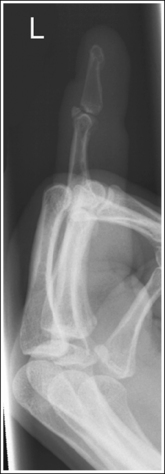

Thumb: Anteroposterior Projection

Thumb: Posteroanterior Oblique Projection

See Figures 4-12 and 4-13 and Box 4-5.

The first digit demonstrates an AP projection. The concavity on both sides of the phalangeal and metacarpal midshafts is equal, as is soft tissue width on both sides of the phalanges.

• An AP projection is accomplished by internally rotating the patient's hand until the thumb is positioned in an AP projection (Figure 4-14). The thumbnail can be used as a reference to determine when the thumb is truly placed in an AP projection. The nail should be positioned directly against the IR and should not be visible on either side of the thumb. A nonrotated AP thumb projection demonstrates equal concavity on both sides of the phalangeal and metacarpal midshafts, as well as equal soft tissue widths on both sides of the phalanges.

• Detecting thumb rotation.When the thumb is rotated away from an AP projection, the amount of midshaft concavity increases on the side of the thumb toward which the anterior surface rotates and decreases on the side toward which the posterior surface rotates. The same observation can be made about the soft tissue surrounding the phalanges when the thumb is rotated. More soft tissue width is evident on the side toward which the anterior surface is rotated, and less soft tissue width is seen on the side toward which the posterior surface is rotated (see Image 10).

The long axis of the thumb is aligned with the long axis of the collimated field.

• Aligning the long axis of the thumb with the long axis of the collimator's longitudinal light line enables you to collimate tightly without clipping the distal phalanx or proximal metacarpal (see Image 11).

The IP, MP, and carpometacarpal (CM) joints are visible as open joint spaces, and the phalanges are not foreshortened.

• The IP, MP, and CM joint spaces are open, and the phalanges are demonstrated without foreshortening as long as the thumb is positioned flat against and placed parallel with the IR and the central ray was perpendicular to and centered with the MP joint space. This positioning aligns the joint spaces parallel with the central ray and perpendicular to the IR and positions the long axes of the phalanges perpendicular to the central ray and parallel with the IR. These relationships change when the thumb is flexed or posteriorly extended (hitchhiker's thumb) for the image. Thumb flexion and extension foreshorten the phalanges and superimpose them over the joint spaces (see Image 12).

Superimposition of the medial palm soft tissue over the proximal first metacarpal and the CM joint is minimal.

• Minimal soft tissue overlap occurs when the medial palm surface is drawn away from the thumb. It may be necessary to use the patient's other hand as an immobilization device to maintain good positioning of the medial palmar surface. If the medial surface of the palm is not drawn away from the thumb, the soft tissue and possibly the fourth and fifth metacarpals obscure the proximal first metacarpal and CM joint (see Image 13).

The MP joint is at the center of the exposure field. The distal and proximal phalanges, the metacarpal, and the CM joint are included within the collimated field.

• Center a perpendicular central ray to the MP joint, which is located where the palm's interconnecting skin attaches to the thumb, to place it in the center of the image. Open the longitudinal collimation to include the distal phalanx and CM joint. Transversely collimate to within 0.5 inch (1.25 cm) of the thumb skin line.

See Figures 4-16 and 4-17 and Box 4-6.

The thumb demonstrates a lateral projection. The anterior aspect of the proximal phalanx and metacarpal demonstrates midshaft concavity, and the posterior aspect of the proximal phalanx and metacarpal demonstrates slight convexity.

• To accomplish a lateral thumb projection, place the patient's hand flat against the IR; then flex the hand and fingers only until the thumb naturally rolls into a lateral projection (Figure 4-18). Overflexion causes superimposition of the second and third proximal metacarpals onto the proximal first metacarpal, obscuring it (see Image 14). When the hand and fingers are accurately flexed and the thumb is in a lateral projection, the midshaft of the proximal phalanx and metacarpal demonstrates concavity on their anterior aspects and convexity on their posterior aspects. If the patient's hand is not rotated enough to place the thumb in a lateral projection, the posterior aspects of these midshafts show some degree of concavity (see Image 15).

The IP, MP, and CM joints are visible as open spaces, and the phalanges are not foreshortened.

• The IP, MP, and CM joints are open and the phalanges are visible without foreshortening if the entire thumb rests against and is positioned parallel with the IR and a perpendicular central ray is centered to the MP joint.

The proximal first metacarpal is only slightly superimposed by the proximal second metacarpal.

• Whenever possible, the anatomic part of interest should be demonstrated without superimposition. For a lateral thumb projection, the proximal metacarpal can be demonstrated with only a very small amount of superimposition if the thumb is abducted away from the palm. Failure to abduct the thumb results in a significant amount of first and second proximal metacarpal overlap and obstruction of the CM joint (see Image 16).

The first MP joint is at the center of the exposure field. The distal and proximal phalanges, the metacarpal, and the CM joint are included within the collimated field.